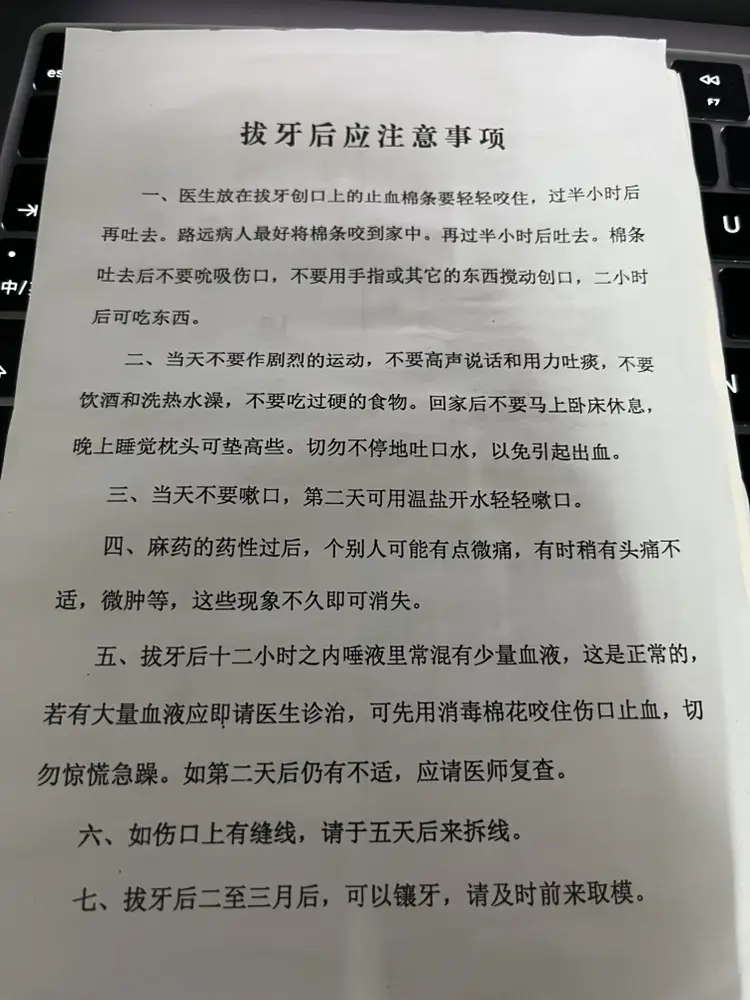

术后给我发了一张小纸条,我就回家了: